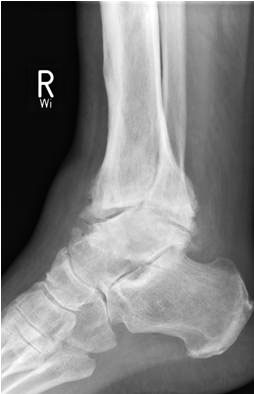

• Primäre oder posttraumatische Arthrose des OSG und USG (Abbildung 1, Abbildung 2).

• Standard-Röntgendiagnostik des oberen und unteren Sprunggelenkes: anterior-posteriorer und seitlicher Strahlengang.